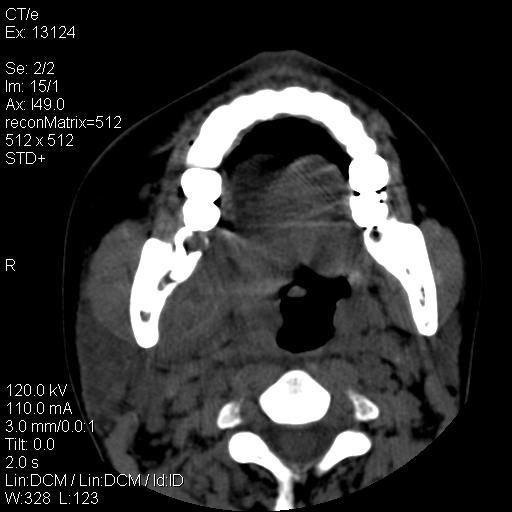

女,29岁,右下磨牙痛,因产后2月,故未治疗。现右颌肿痛伴张口困难。请大家看看右侧鼻咽部、口咽部是否

1.考虑右侧下颌区脓肿(牙源性)

考虑右下智齿冠周炎伴周围软组织炎症,脓肿形成

1)考虑右侧下颌区软组织脓肿(牙源性)。2)鼻咽部炎性改变;建议追踪复查。3)右侧上颌窦炎。4)双侧下鼻甲黏膜肥厚。

1)考虑右侧下颌区牙源性软组织脓肿。2)右侧上颌窦炎。3)双侧下鼻甲黏膜肥厚。4)鼻咽部炎性改变;建议追踪复查。

考虑右下智齿冠周炎伴周围软组织脓肿形成。